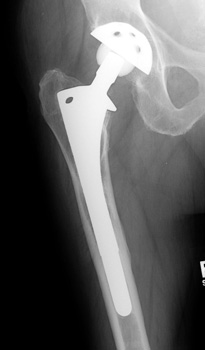

• Cemented

Cemented